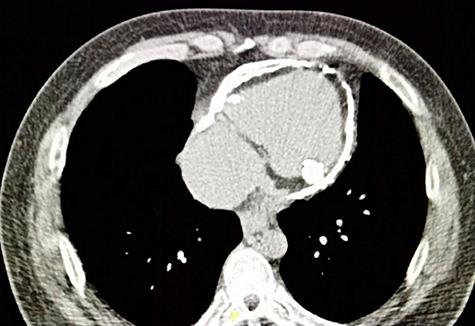

Constrictive pericarditis is a disabling disease of the heart, which causes cardiac diastolic dysfunction. We present a case of a 44-year-old gentleman with a history of blunt chest trauma who presented with constrictive pericarditis with right-sided heart failure. Imaging studies revealed a calcified pericardium. He underwent an uneventful pericardiectomy. Calcification is common yet rare if it involves the pericardium. It normally occurs following fibrosis and adhesion which are associated with the chronicity of the disease, hence creating more challenge to the operating surgeon in the pericardiectomy procedure.